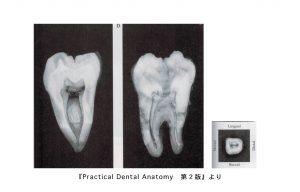

上顎大臼歯の中身

• 歯の外形を縮小した形。

• 髄室角は近心頬側で最も鋭く突出する。

• 根管数は3〜4根管、あるいは2〜1根管認められる。

• 頬側根管は細く彎曲するものから幅広いものまで認められる。

• 近心頬側根管では2根管が50%存在する。